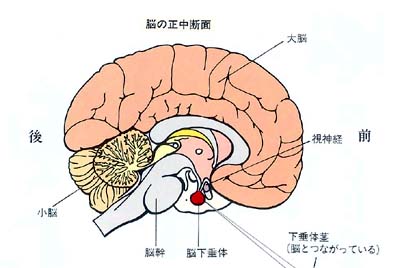

肝臓、腎臓等と違って、日常ほとんど聞き慣れない言葉だと思います。これは、読んで字のごとく、「脳からぶらさがっている器官」のことで、実際は脳の下面と細い茎(これを下垂体茎といいます)でつながっているため、このように呼ばれます。

脳下垂体はどこにあるのか?とよく聞かれますが、およそ首から上のいわゆる頭蓋骨のほぼ中心に位置します。別のいい方をすれば、眉間の奥7cm前後のところにあります。

脳下垂体のすぐ中上には左右の視神経とその交叉部があります。また、脳下垂体の左右には海綿静脈洞という太い静脈があり、その中を内頸動脈という太い動脈や眼球を動かす神経などが走っています。正常な脳下垂体は 「女性の小指の先端」くらいの大きさで、重さは1gもありません。 これはさらに前葉と後葉の2部に分かれており、前者が大きな容積を占めています。